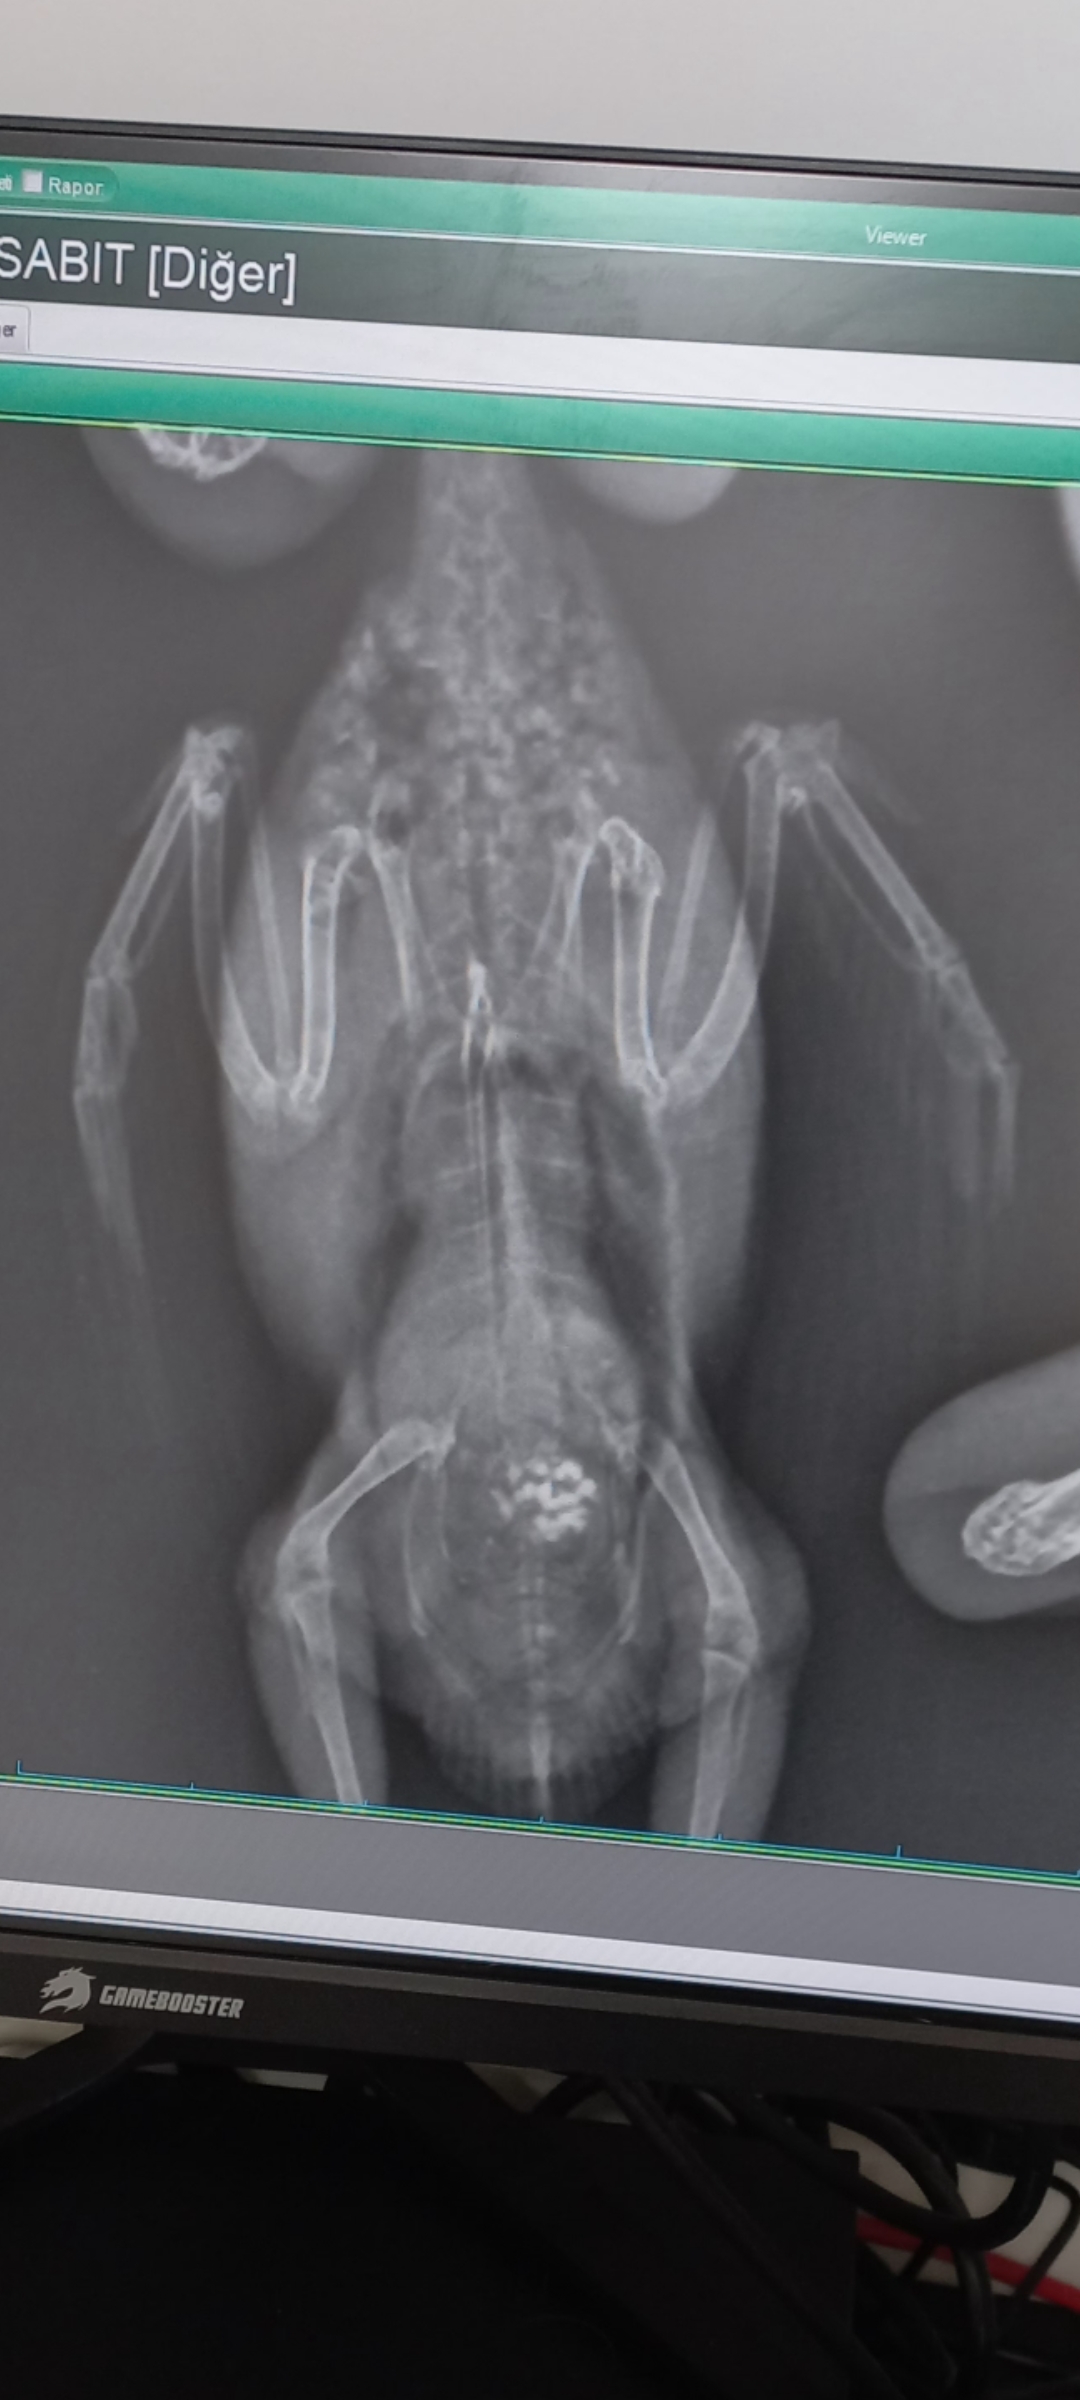

Burada röntgeni. Bu sıralar ayakları da soğuk, sindirimi sıkıntılı. Karaciğer sıkıntısından dolayı bunlar olabiliyormuş diye okudum. Dışkısı da arada yeşil leke bırakıyor, safradan dolayı olabiliyormuş. Metabolizma yavaşladığı için sindirim de yavaşlayabiliyormuş. 1 haftadır sadece geceleri yem kustu en son 1 kez salyalı kusunca hekim kursak hareketini destekleyen bir ilaç verdi 3 gün kullandık 2 gündür kusmuyor sadece parça parça arada kusuyor. O zaman anladım, muhtemelen yemler kursağında olması gerekenden uzun süre kalıyor. e gece de hareketsiz olduğundan sindirim doğal olarak yavaş zaten, bundan dolayı daha da yavaşlıyor. ilaç da kursak hareketini destekliyor. anında kusmayı kesince anladım. gün içinde hareketli gayet yemini suyunu içiyor, hatta az önce hepacarnitollu suyu aldık temiz su koydum az önce içti. Araştırdım karaciğersel sorunlarda bunlar olabiliyormuş zincirleme şekilde. Zaten nefes sorunu da var. Ben de beklemeden hemen kullanmak istedim. Yakın zamanda epey ilaç yükü de oldu 🥲

Röntgende Belirgin Karaciger Büyümesi var. Kaç Gram Peki Şuan Yavrunuz ?

zayıf 🥲 yanlış tedavi uygulandı ilaç yüküne soktum kuşu, şu an o ilaç yüklerinden olduğunu düşündüğüm sorunları düzeltmeye çalışıyorum. ilk gittiğimizde 32 gramdı, sonra 1 gram aldı. bu kusma başlayınca birden kilo kaybetti 30a düştü. şimdi 31 gram. verdiği kilodan 1 gram aldı geri. yavaş yavaş toparlayacağım kızımı. Yani garip bir şekilde sadece gece kusma-öğürme hareketi yapıyor. Ben dediğim gibi yukarıda yazmıştım, karaciğer sorunu sindirim sistemini bozabiliyormuş, metabolizmayı yavaşlatabiliyormuş. kanın temizlenmesinden görev alıyormuş sanırım. bu fonksiyonlar bozulunca sindirim sorunları, üşüme, halsizlik vs görülebiliyormuş. nefes sesleri hala devam ediyor ama şu an bu öğürme-kusma durumunu düzeltmeye çalışıyorum. 2 gecedir kusmuyor sadece ağzına yemi getirip yiyor toz şeklinde dökülüyor yem dökülüyor.

biraz araştırdım dediğim gibi gece zaten metabolizma yavaşlıyormuş, e karaciğerde sorun olunca ek olarak yavaşlıyor ve sadece gece görülem öğürme-kusma davranışı olarak yansıyor. enerji dengesi de bozulabiliyormuş, toksinler düzgün atılamıyormuş. bunun sonucunda ayaklarındaki soğukluk olabilirmiş. birden başlayan bu durumu ben karaciğere bağladım çünkü bir enfeksiyon olsa kuşum halsiz olur yani. inşallah hepacarnitol bunları iyileştirecek. 10 günde karaciğerin çalışmasına gözle görülen bir fark olur mu bilmiyorum ama dua edeceğim.

hatta veterinere sorduğumda kuşum hep zayıftı yağlanmadan dolayı olmuyor mu bu büyüme diye. bana zayıf kuşlarda da karaciğer büyümesi görüldüğünü söyledi ve nadir olmadığını söyledi. ve fazla bir büyüme değil dedi.

Şehmus beye atmıştım o da 2 hava kesesi kapalı demişti 🙏🏼 ama bir dakika, bu yağlanmadan dolayı mıdır? büyüme yani. siz şu an böyle deyince ümitlendim yağlanma ise geri alınabilir değil mi?

Karaciğer Yaglanmasi Ve Büyümesi Hemen Hemen Aynı Şeyler. Çok Büyük Olduğunda Organ Hasarı Oluyor. Tedaviside Zor Oluyor. Hava Kesesi Kapali Olmasının Karaciğer Kaynaklı Değildir. Karaciğer Büyüdükçe Baskı yapar Organlara. Odada Biraz Nemlendirici Kullanin ve Isıyı Çok İyi Ayarlayın.

Hava kesesi kapanması karaciğer büyüdüğü için olmaz mı? o zaman neden olur ki? Yani büyüme yağlanma sebepli ise hepacarnitol bunu büyük ölçüde düzeltemez mi o zaman? ben yağlanma değil de başka bir sebeple büyüdü sanmıştım büyümeyi. bizimki çok büyük değilmiş hafif büyüme varmış.

Karaciğer yanlış beslenme, genetik, hareketsizlik gibi faktörlerden büyür, karaciğerin etrafındaki hava kesesine büyüdükçe baskı yapar. Ezgi ablanın demek istediği hepacarnitol kuşunuza kilo verdirecek güçten düşmesin diye ek olarak da elle besleyin demek istemiş